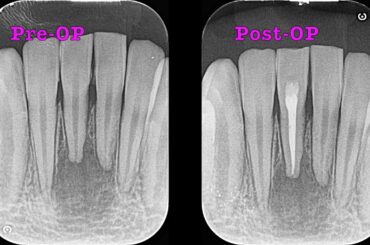

当院の「精密根管治療(初回:感染根管治療)」の予後観察についてご紹介します。…